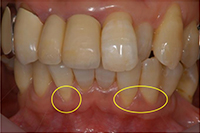

治療前の状態です。

歯ぐきが退縮し(歯ぐきが下がり)、歯の根が露出しています。 -